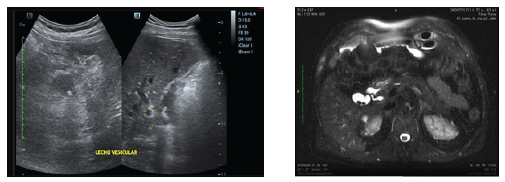

Acude al servicio de emergencia de la casa de salud en cuestión por presentar meteorismo abdominal, dolor en hipocondrio derecho, además de dispepsia, en correspondencia al cuadro clínico, se solicita ecografía de abdomen que evidencia lecho vesicular con cálculos en su interior, adicional refiere haberse realizado resonancia magnética por control de sus patologías de base, en el mencionado estudio se da el hallazgo incidental de colelitiasis del remanente, de tal forma que se decide su ingreso para resolución quirúrgica, (Figura 1A y B).

Figura 1A. El lecho vesicular con presencia de imagen anecoica con múltiples cálculos en su interior, el de mayor tamaño mide 6.5 mm, hallazgos que ante el antecedente quirúrgico colecistectomía pudiera corresponder con dilatación del conducto cístico. B. Corte axial: Flecha blanca muestra la presencia de litiasis en remanente vesicular en resonancia magnética.

Por tanto, para ajustar un acertado diagnóstico de este síndrome poco reportado, es necesario realizar una adecuada anamnesis, basada en los antecedentes patológicos del paciente, sus antecedentes quirúrgicos, será determinante descartar causas extrabiliares, se deberá realizar una analítica completa, y estudios de imagen como la ecografía abdominal, este estudio manifiesta imágenes nodulares o lineales hiperecogénicas con sombra acústica posterior correspondientes con litiasis, la TAC evidencia lesiones heterogéneas de predominio hipodenso, con calcificaciones en su interior y realce periférico posterior a la administración de material de contraste , o inclusive se pueden dar hallazgos incidentales en estudios de mayor rango como lo es la resonancia magnética, tal cual se reporta en este caso (13,14).